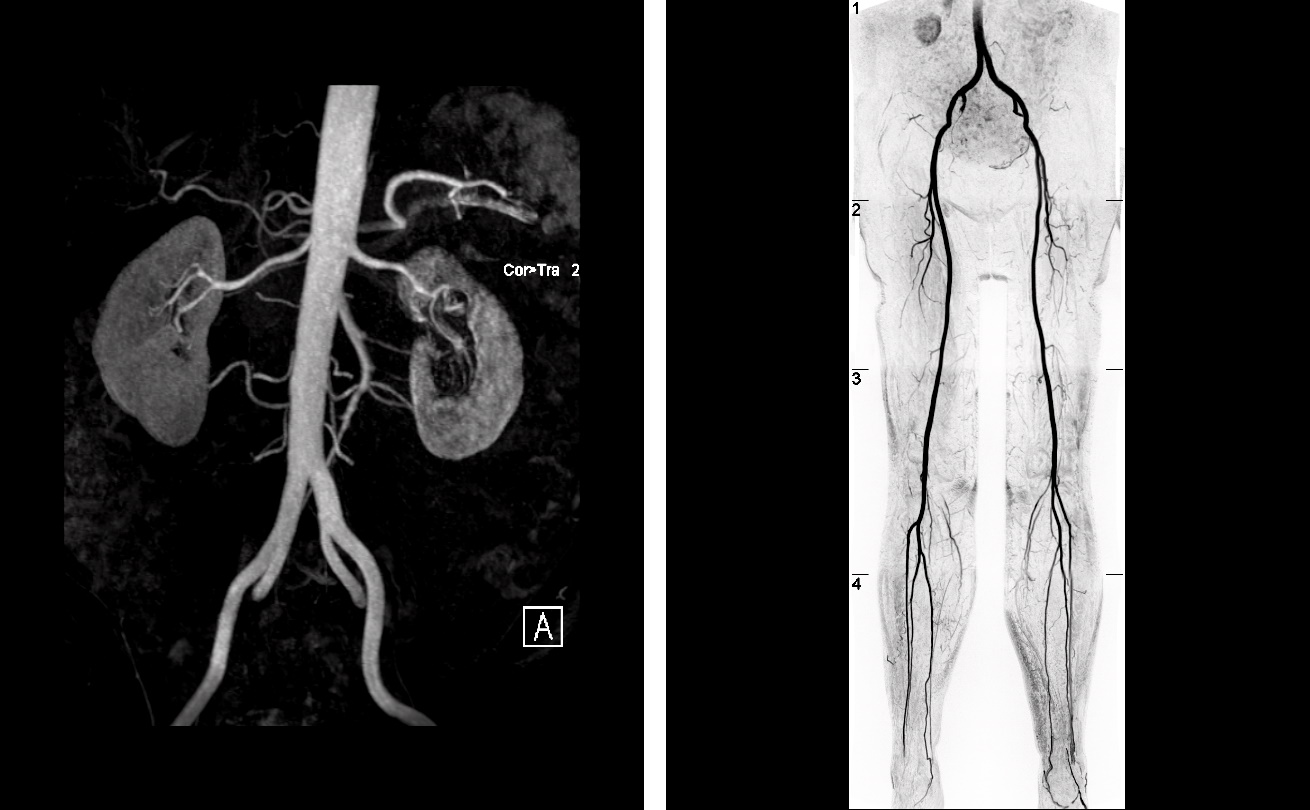

Mit der Kernspintomographie von Gefäßsystemen, der sog. MRT-Angiographie können sowohl große Schlagadern als auch kleinste blutführende Gefäße im Körper zuverlässig dargestellt und beurteilt werden. Dadurch werden Ablagerungen an den Gefäßwänden durch unsere Radiologen frühzeitig erkannt, die im fortgeschrittenen Stadium z.B. zu Schlaganfällen oder arteriellen Verschlusskrankheiten (pAVK/“Schaufensterkrankheit“) führen können.

Mit der Kernspintomographie lässt sich Ihr Gefäß-Check ohne jegliche Strahlenbelastung durchführen. Das schnelle und schmerzfreie Verfahren lässt frühzeitig Gefäßengstellen, Unregelmäßigkeit der Gefäßwände, drohende Verschlüsse und Aneurysmen abbilden und beurteilen, um deren möglicherweise gravierenden Folgen vorzubeugen.

Je nach individuellem Untersuchungsprogramm werden wir bestimmte Gefäßabschnitte untersuchen.

- Gefäß-Check der Hauptschlagader (Aorta)

- Gefäß-Check der Nierenarterien

- Gefäß-Check der Becken- und Beingefäße